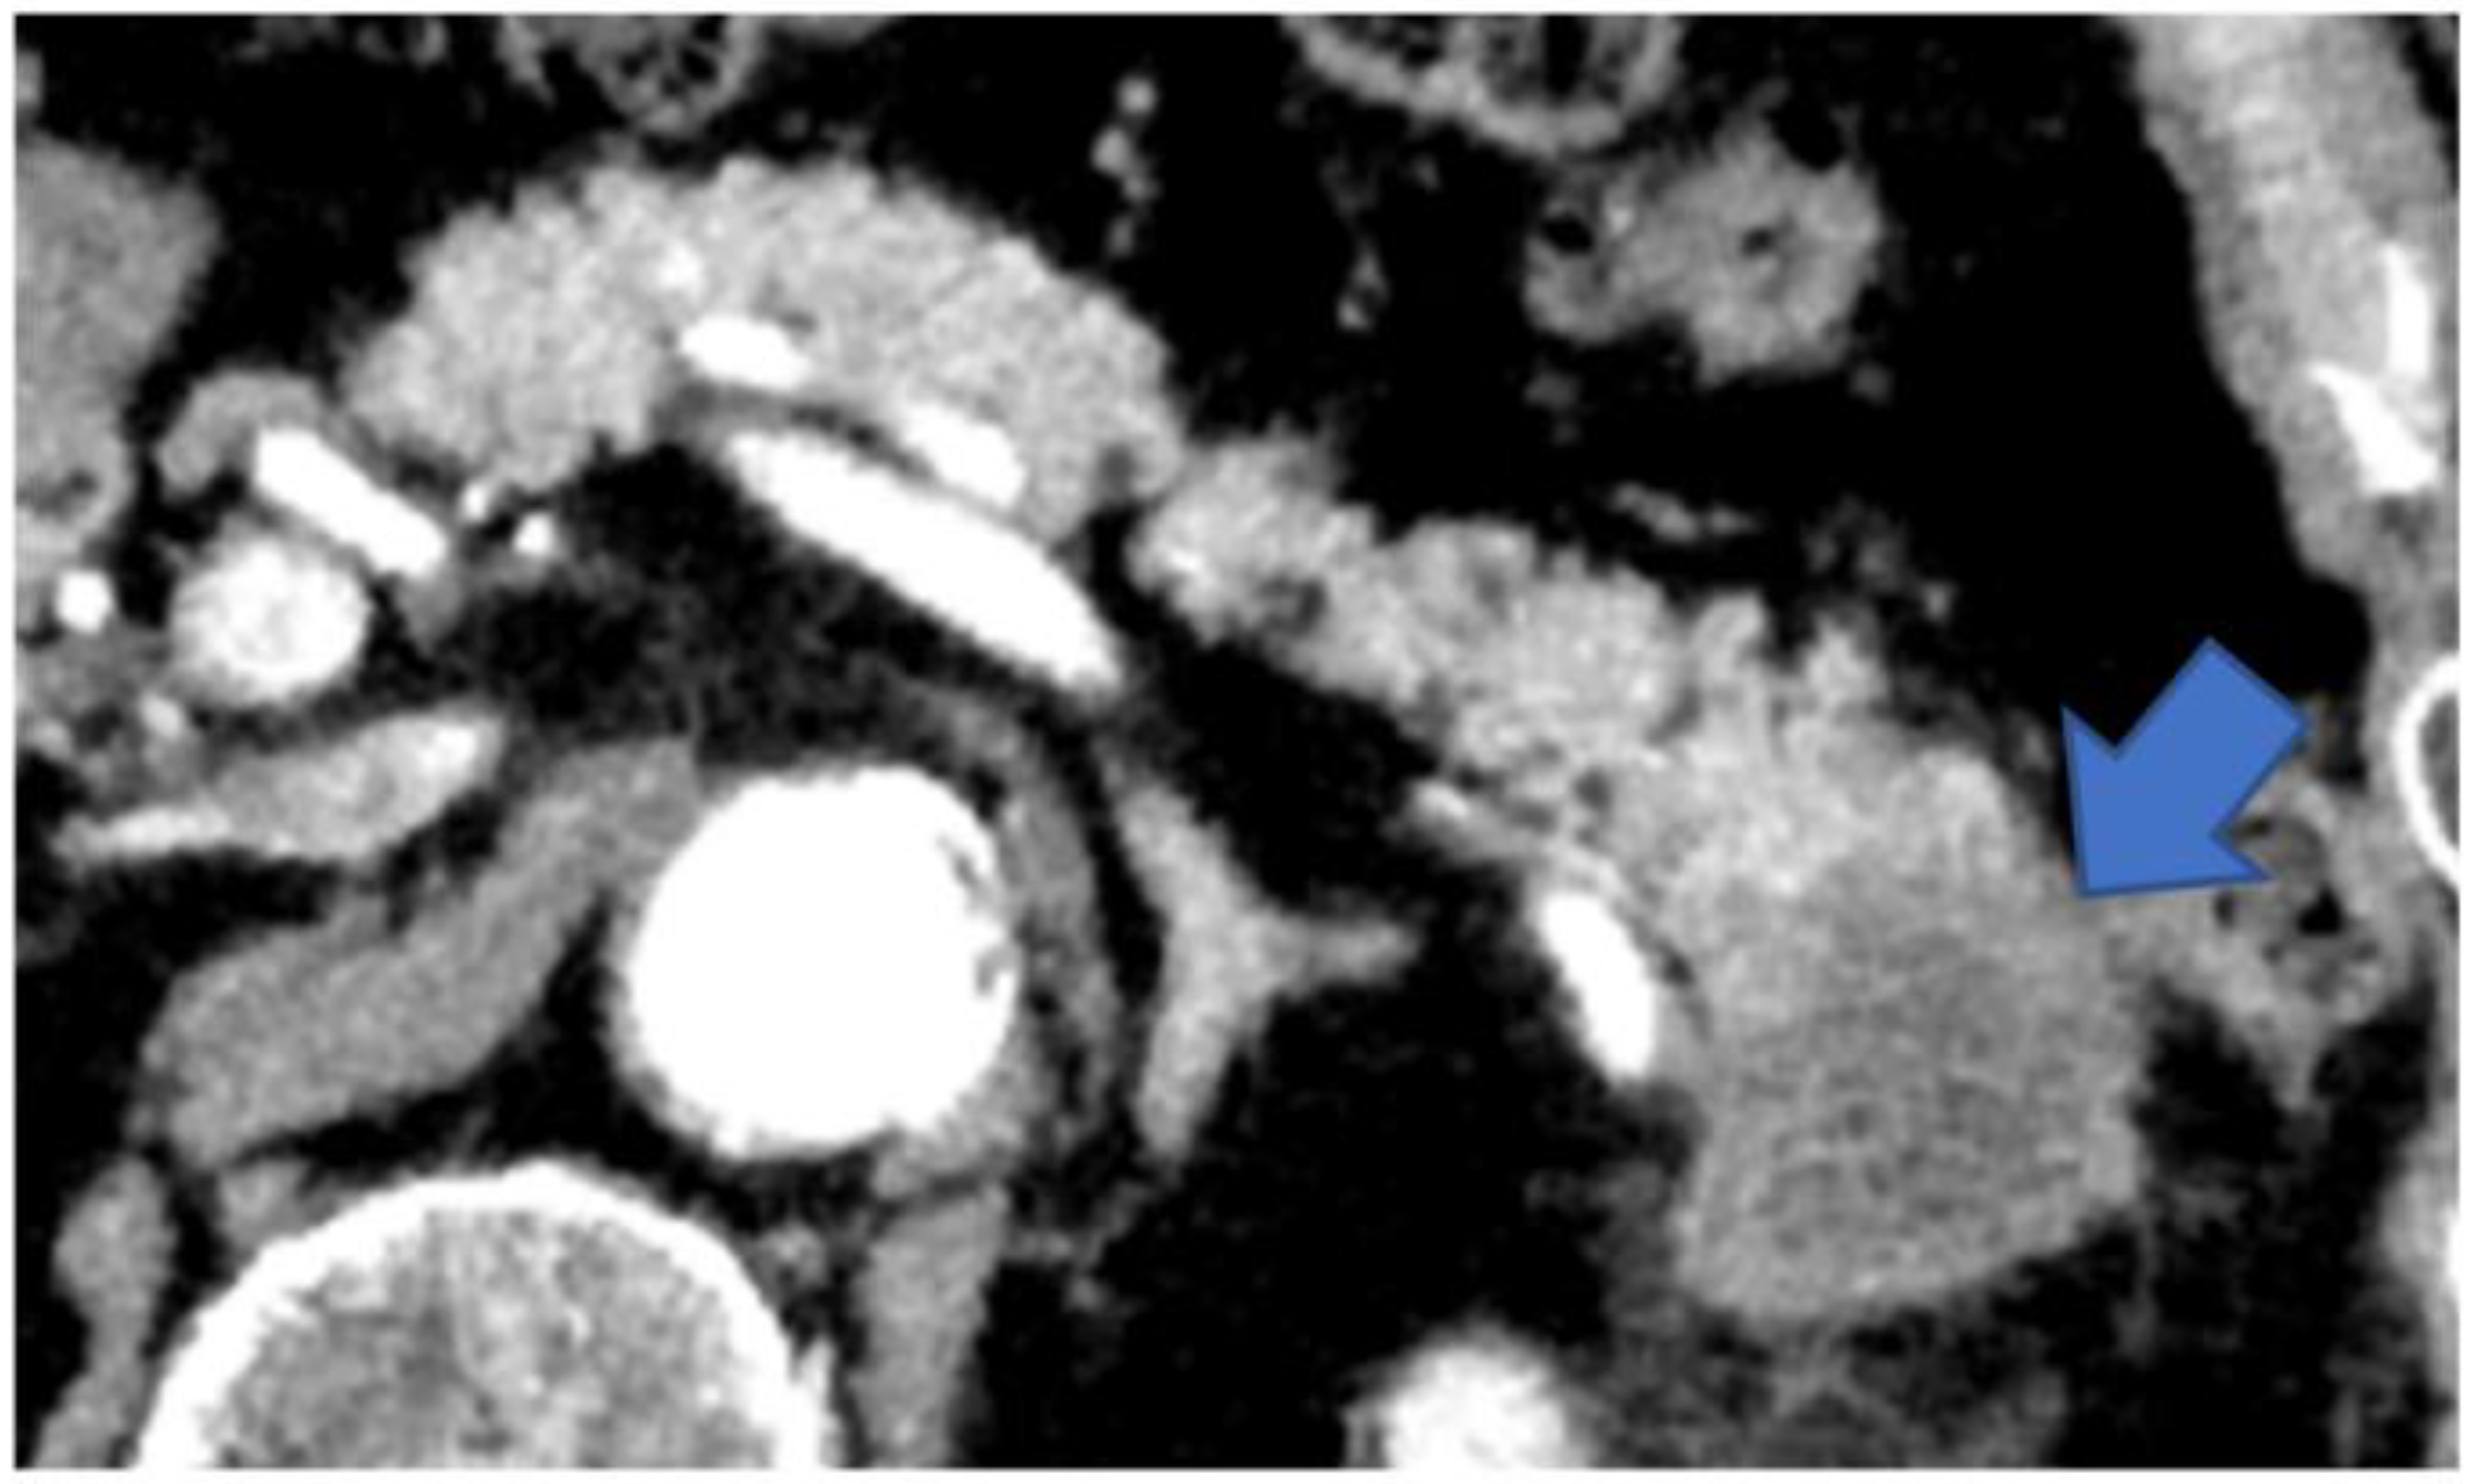

3.3. Imaging Findings